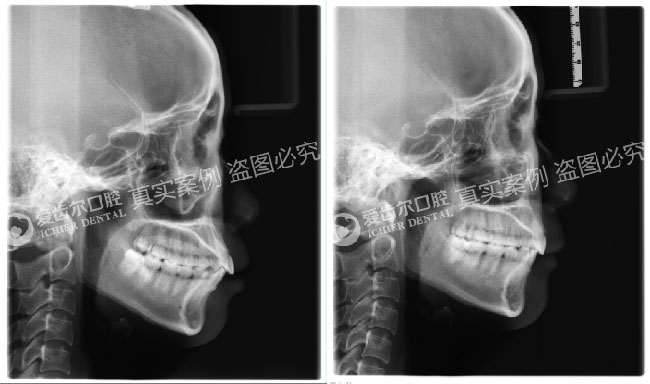

矫正前后头颅侧位片